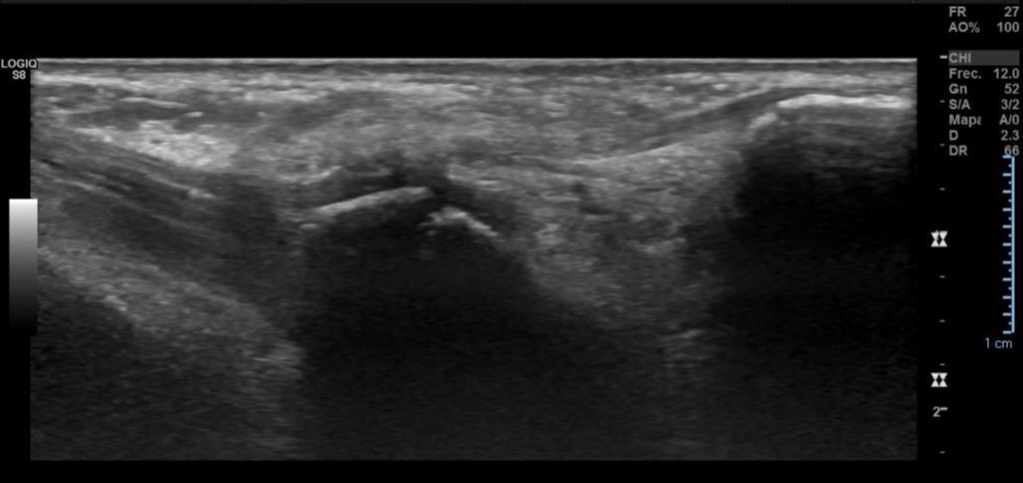

Engrosamiento y disminución de ecogenicidad del tendón peroneo largo en su región distal, sin desgarros.

Imagen con aspecto de os peroneo de contornos corticales irregulares, con cambios inflamatorios de las partes blandas adyacentes, pudiendo estar en relación a fractura a este nivel.

Impresión diagnóstica: Imagen con aspecto de os peroneo de contornos corticales irregulares, con cambios inflamatorios de las partes blandas adyacentes, pudiendo estar en relación a fractura a este nivel. Se sugiere evaluar con radiografía.

Tendinosis del peroneo largo en su región distal.